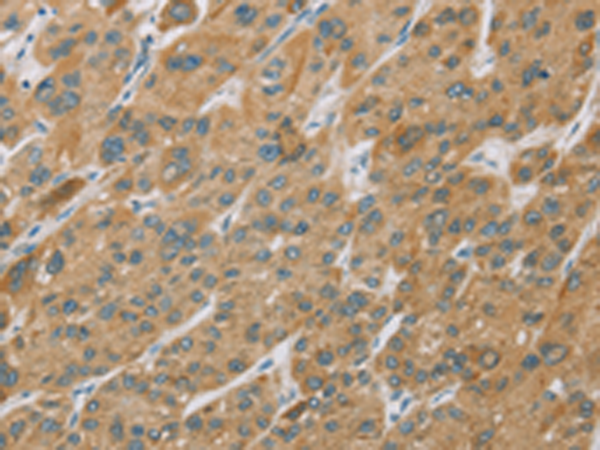

分类: 科研抗体货号: P08209别名:应用: WB,IHC反应种属: Human